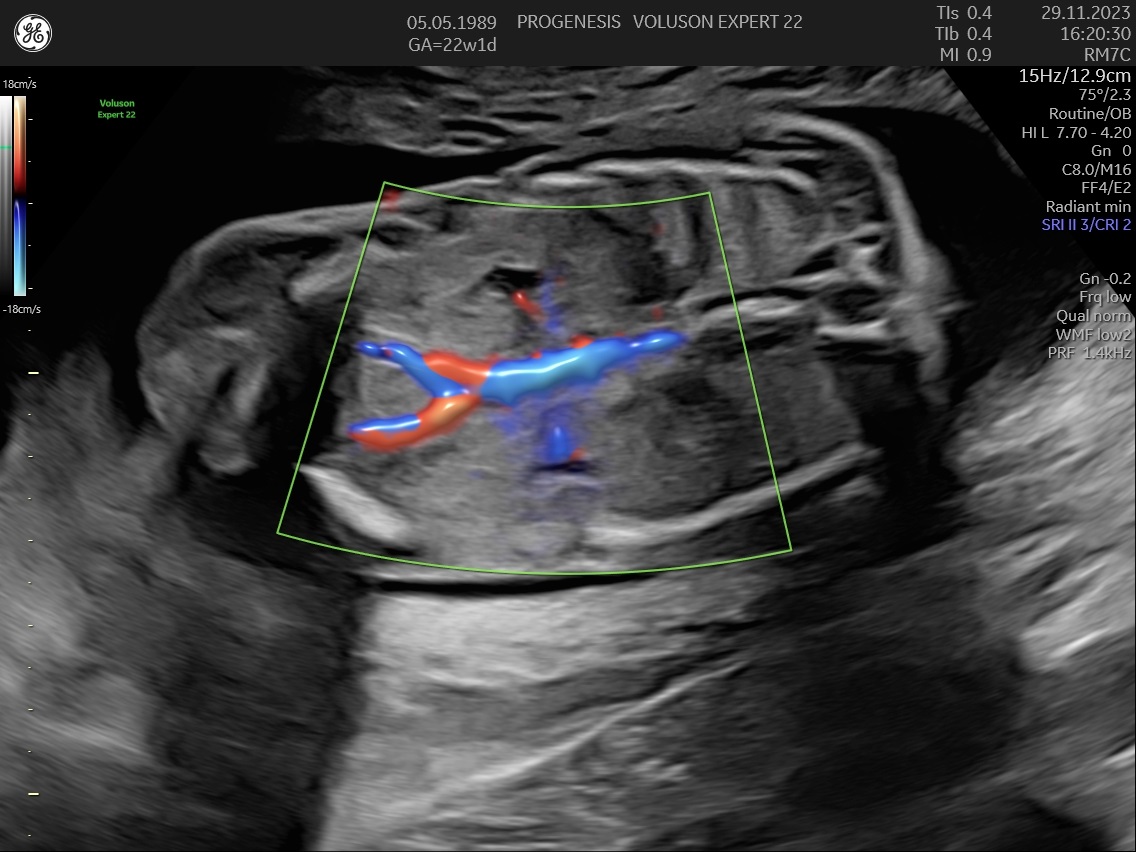

ε) Ο υπολογισμός της πιθανότητας προεκλαμψίας και ενδομήτριας καθυστέρησης της ανάπτυξης του εμβρύου.

Η μέτρηση των αντιστάσεων στις αρτηρίες της μήτρας, θα εντοπίσει τις μητέρες που έχουν αυξημένη πιθανότητα να εμφανίσουν υπέρταση ή προεκλαμψία στη κύηση ή και πλακουντιακή δυσλειτουργία που θα οδηγήσει σε ελλάτωση της εμβρυϊκής ανάπτυξης (μικρό έμβρυο).